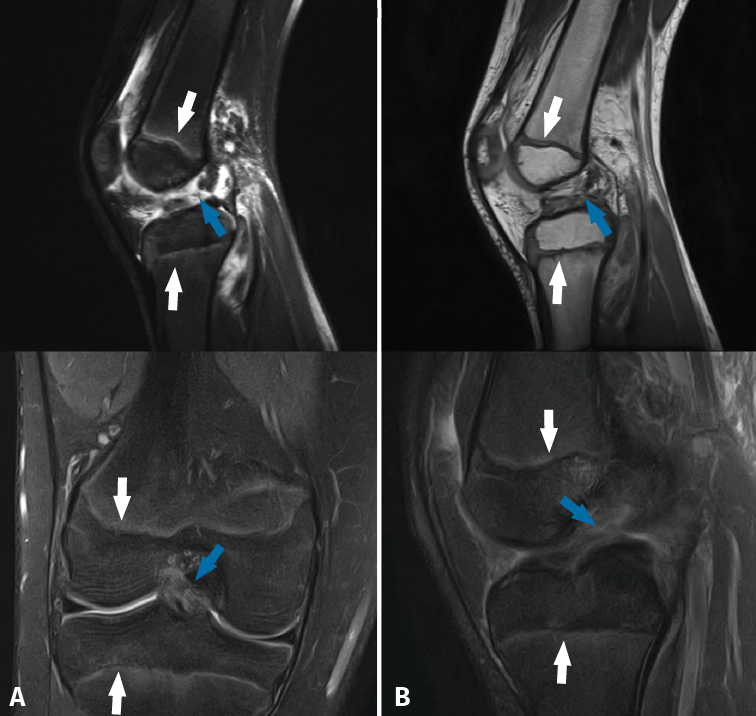

Magnetic resonance imaging shows the physes in great detail in both the distal femur and in the proximal tibia (Figure 3), and is the best technique for evaluating them(30). The presence of the physes can complicate the diagnosis of ligament lesions in immature patients(32).

Magnetic resonance imaging allows precise assessment of the physeal condition of the patient(33). Physeal closure is directly proportional to age, though there are differences according to gender(28). Physeal closure is 0% until 11 years of age, 5% at 12 years, 34% at 13 years, 53% at 14 years, 94% at 15 years, and 100% from age 16 (33): this means that growth is complete in girls at about 14 years of age and in boys at approximately 16 years of age. Furthermore, the central portion of the physis of the proximal tibia closes before the peripheral portion - this fact being important for positioning of the tibial tunnel in ACL reconstruction.

Figure 3. Magnetic resonance imaging views of the knee in two children with open physes (white arrows), presenting rupture of the anterior cruciate ligament (blue arrow).